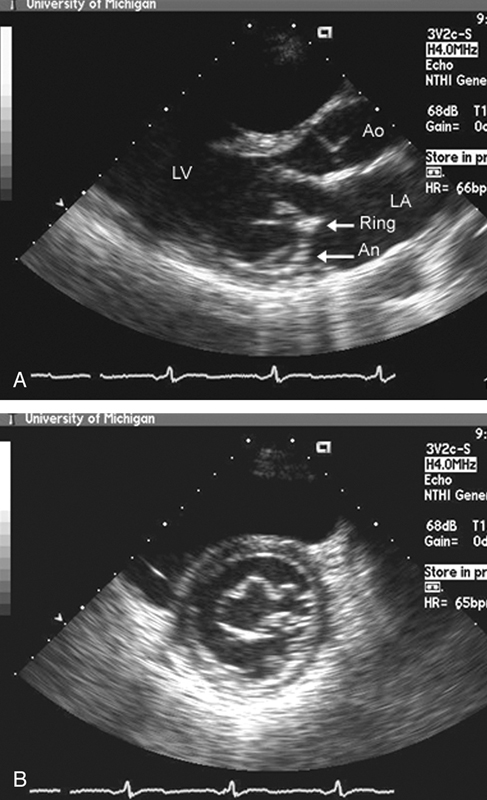

فحوصات تشخيصية لبعض امراض القلب والشرايين التاجية